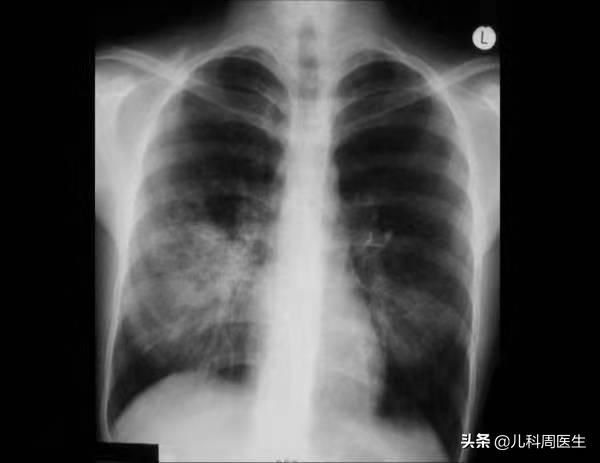

小儿支原体肺炎胸片改变

医生当然不会拿这种非特异性检查作为诊断依据的,一般是通过询问病史、了解临床特征来初步判断,比如咳嗽持续2~3周、且进行性加重;一般抗生素治疗均无效,临床咳嗽剧烈而肺部往往听不到啰音。然而,要诊断支原体肺炎就要依据胸片+病原学检测。